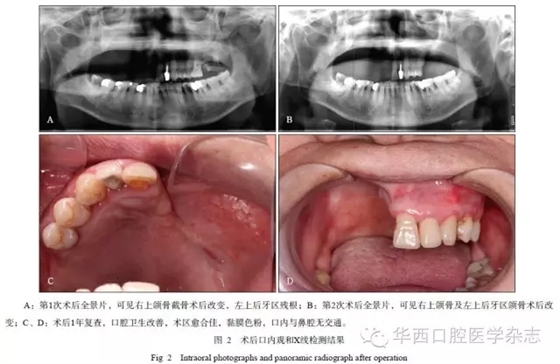

患者女,72歲,乳腺癌個人史20年、肺轉移13年。肺部轉移后,患者長期接受化療,接受過肺部放療?;颊呒韧酗嬀剖罚咳诊嫲拙?0mL,共飲6年,已戒20年;無抽煙習慣。2012年4月發現骨轉移后開始使用唑來膦酸,至入院前共計使用4mg×28個月。出現口腔癥狀(圖1)后行局部及全身抗炎治療,并接受了18次高壓氧倉治療。患者入院后,接受“上頜骨部分切除術”,術后愈合可。3個月后,左上頜后牙區再次發生藥物性頜骨骨髓炎,遂入院接受手術治療,術后愈合佳(圖2)。

640.webp (1).jpg

640.webp (2).jpg